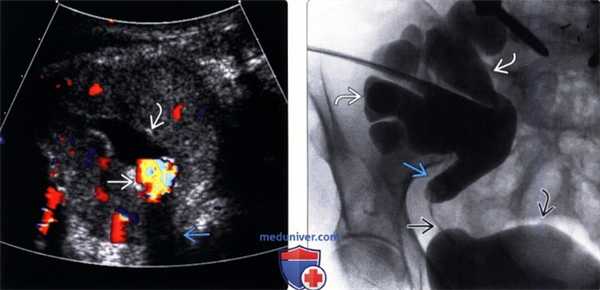

(Левый) На продольном трансабдоминальном ультразвуковом срезе визуализируется расширение чашечно-лоханочной системы почки. Выраженное истончение паренхимы указывает на длительно текущий процесс.

(Правый) На ультразвуковом срезе с цветовой допплерографией у того же пациента ИР = 0,7 (в пределах нормы), что согласуется с хроническим течением тяжелого гидронефроза у данного пациента.

(Левый) На продольном УЗ срезе трансплантата почки визуализируется дилатация почечной лоханки и чашечек, обусловленная протяженной стриктурой мочеточника.

(Правый) В MIP-режиме КТ антеградной нефростомографии у этого же пациента визуализируется тяжелый гидронефроз трансплантата почки. Имеется протяженная фиброзная стриктура мочеточника трансплантата. Требуется хирургическая реконструкция.